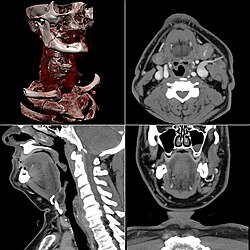

Craniale Computertomographie Abgebildet sind Felsenbein und Nasennebenhöhlen. Aufgrund der hohen Auflösung der Aufnahme des verwendeten 64-Zeilen-CTs sind selbst die Gehörknöchelchen erkennbar. -

Koronal reformatierte Darstellung von Abdomen und Becken; gut zu erkennen sind u. a. die Leber und die beiden Nieren. -

Kombination aus multiplanarer Reformatierung und sliding thin slab. Der Bildkursor befindet sich in der Harnblase. Die Originalschichtdicke beträgt 1,25 mm, dargestellt wird in allen Ansichten gemittelt (= average) in 3,7 mm bzw. 3,8 mm Dicke. -

Kombination aus multiplanarer Reformatierung und sliding thin slab. Der Bildkursor befindet sich im rechten Lungenflügel. Die sts-Bildstapel werden in Form von MIP-Darstellungen gezeigt (STS-MIP).[52] Links oben befindet sich eine VR-Darstellung der Lunge; sie zeigt einen Blick auf die koronal an Kursorposition geschnittene Lunge. -